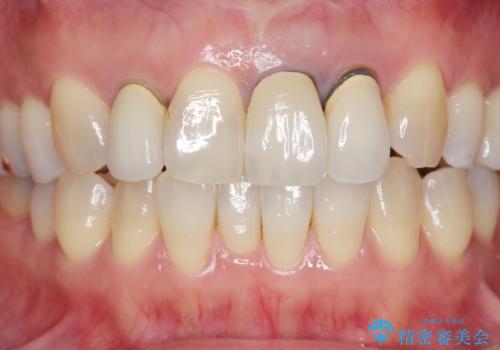

周囲の歯に調和したセラミッククラウンを作製し、審美性を大幅に向上させることができました。